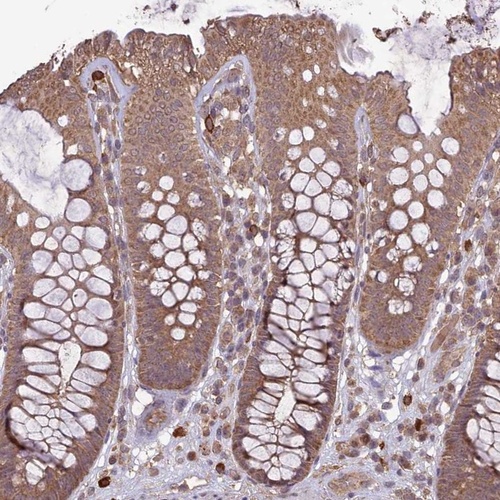

Immunohistochemical staining of human colon shows moderate cytoplasmic positivity in glandular cells.